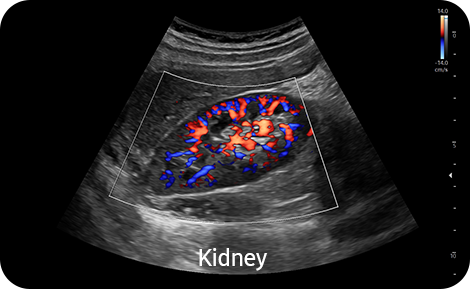

Vyšetření periferních cév směrovým Power Dopplerem |

S-Flow™, směrová technologie Power Doppler, pomáhá detekovat periferní cévy. Umožňuje přesnou diagnózu v případech, kdy je vyšetření krevního průtoku velmi obtížné.

![]()